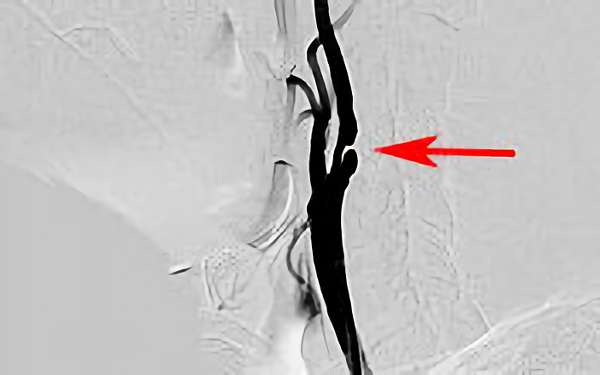

169

'18年7月3日

左内頚動脈狭窄症

70代

院内外来

手術写真

治療

前

中

後